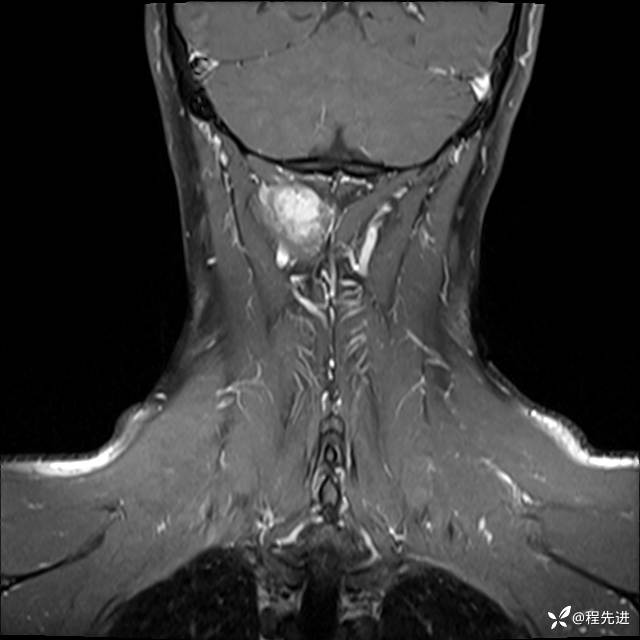

MRI平扫+增强:

T1增强: